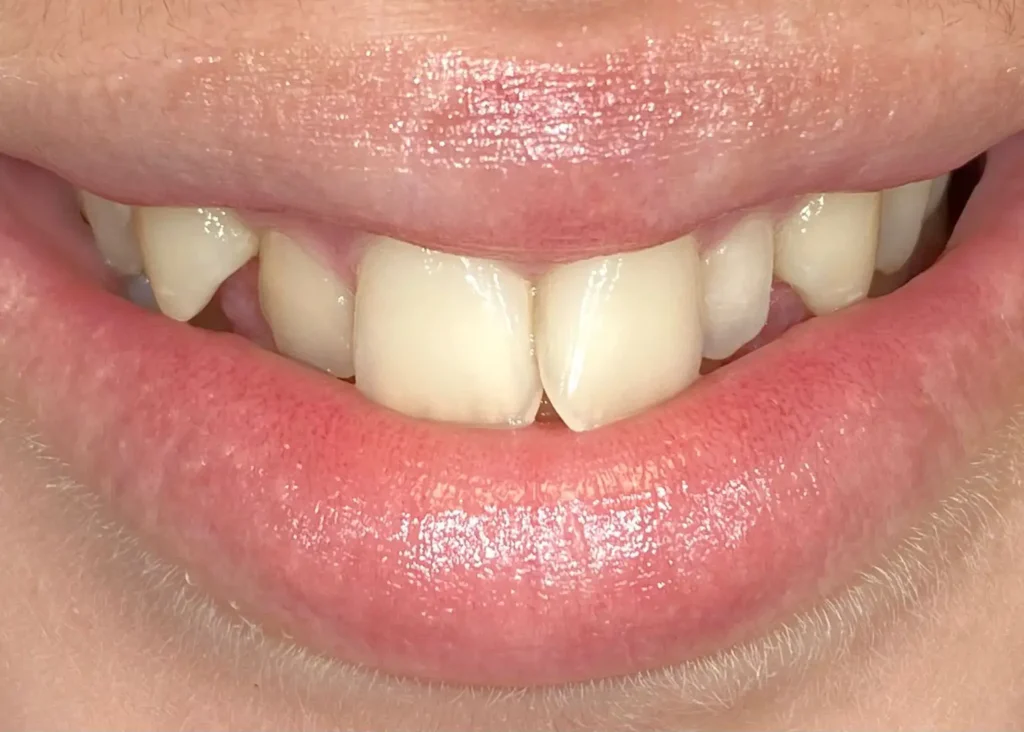

Casos clínicos de ortodoncia en CDPA